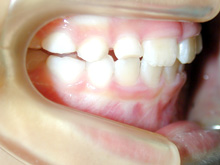

K.S様(女性)

K.S様は下顎前歯の叢生、左側側切歯の舌側転位を主訴として来院されました。

「下顎前歯のなかに入っている歯を治したい」とのことでした。

部分矯正をご希望でしたが、本格矯正の診断と同様に模型採得、

口腔内写真・顔面写真の撮影、レントゲン撮影を行い資料を集め、診断しました。

臼歯関係は良好で部分矯正で治療が可能であることをお話しました。

上下の前歯が緊密に接触していることと、上顎の前歯にも軽度の叢生があるため

上顎の前歯の部分矯正の必要性を説明しました。正中も大きくずれています。

上下顎第2小臼歯までブラケットをつけてワイヤーにて部分矯正を行ないました。

必要に応じてストリッピング(IPR:インタープロキシマルリダクション)を行ないました。

部分矯正ですが上下顎中切歯の正中も治療前に比べて大きく改善しています。

歯列矯正の副作用として治療中のむし歯の発生や歯周病の悪化の危険性以外にも、

歯根吸収、歯根破折、歯髄変性、歯髄壊死などの可能性があり、注意が必要です。

ストリッピングを行なっているのでエナメル質の範囲で隣り合った歯と歯の間の歯質を切削しています。

治療期間:1年2ヶ月

治療費用:43万円